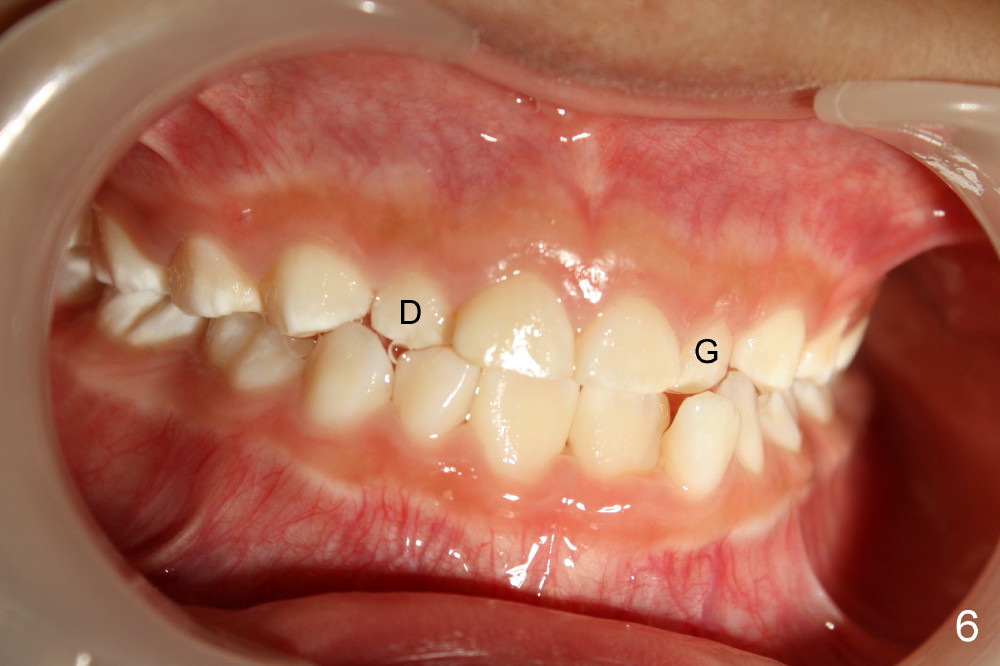

When Devon is 5 years old, there are no spaces between the deciduous teeth (Fig.4-6). The developing upper central incisors are deviated from the midline and off angle (Fig.4: black lines, as compared to Fig.1). Two upper deciduous lateral incisors are in cross bite (Fig.6). LR6 (lower right permanent first molar) rotates (Fig.7 *, as compared to normal LL6 in Fig.8).

当Devon五岁时,没有乳牙间隙(图四至图六),正在发育的恒中切牙不仅远离中线,而且角度不对(图四:斜线,与图一:8,9(恒中切牙)比较)。乳侧切牙反合(图六:D, G)。右下第一恒磨牙扭转(图七:*,与图八:左下相应牙齿对比)。